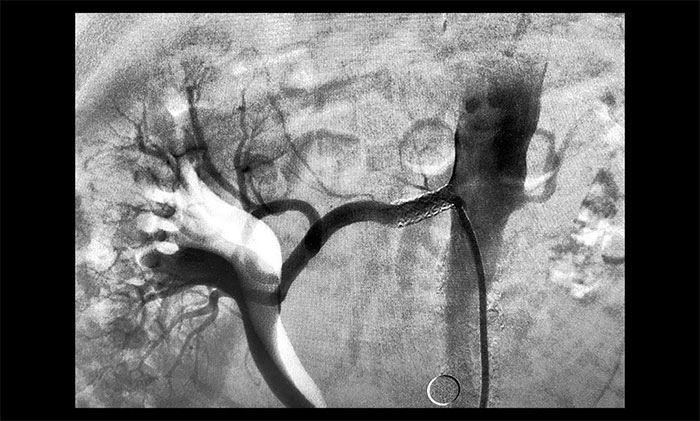

腎動脈位置較為特殊,要順利完成支架置入手術(shù),需要在分毫之間運作導(dǎo)絲完成操作、定位,十分考驗手術(shù)醫(yī)生的技術(shù)手法和臨床經(jīng)驗。席剛明教授團隊充分完善手術(shù)預(yù)案,迎難而上,于2023年12月14日為患者行右側(cè)腎動脈支架置入手術(shù)。一系列精細的操作下,通過球囊擴張改善狹窄,再撤出球囊,將支架于狹窄段擴張釋放……每一步都要既謹慎又到位,術(shù)中造影即可見狹窄明顯改善。歷時近一個小時,手術(shù)順利完成。

▲ 支架置入后狹窄明顯改善